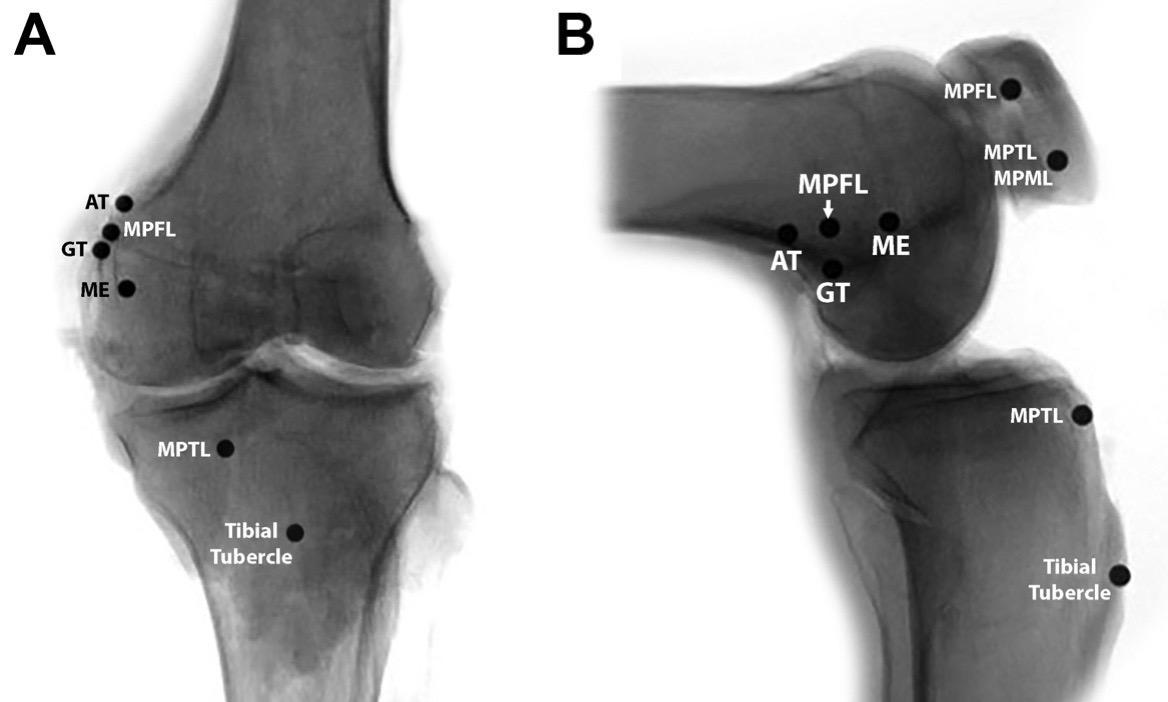

MPFL(内侧髌股韧带)